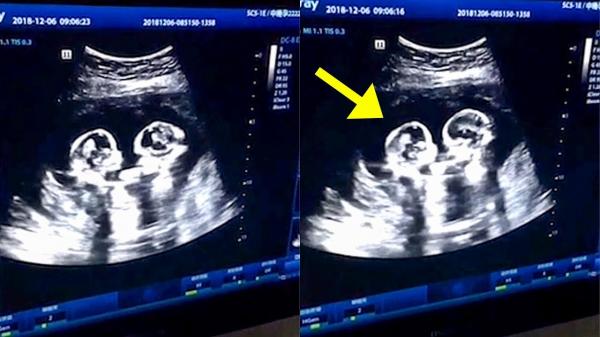

فيديو يصور مشهدا عجيبا لشجار بين توأمين في رحم أمهما